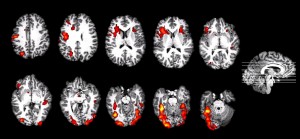

Positron emission tomography (PET) and functional magnetic resonance imaging (fMRI) have been employed in various functions of the medical field including the assembly of research to map the brain’s response to pain and painful stimuli. Functional MRIs provide a unique foundation from which to analyze brain activity, often utilizing blood-oxygen-level dependent (BOLD) contrast as a means of tracing active neurons, and 2013 studies conducted at the University of Colorado Boulder by Tor Wager, PhD, verified the ability of fMRI to distinguish intensities of pain. PET scans, meanwhile, capitalize on metabolic activity of active cells in the presence of a positron-emitting radionuclide in order to compose an image mapping the body’s functioning processes. Though these technologies represent impressive medical advancements, the transformative technology I envision would revolutionize the process of medical treatment and therapeutic decision-making.

Pain by a simple definition is the emotional response to activation of specialized sensory receptors, called nociceptors, that apprise the central nervous system of tissue damage in order to evoke a response or awareness of the affliction. I foresee a radical technology that by a series of imaging techniques inspired by PET scans and fMRIs enables identification of the specific bundle of nociceptors responding to an internal stimulus. Likely through the use of a tracer that illuminates the neurons’ electrical signal, this innovative imaging technique would serve as an indispensable diagnostic tool. Rapid and astonishingly specific diagnoses would facilitate targeted treatments effective in treating patient pain as well as frugal for health care institutions, which could administer necessary treatments without the expenses of numerous diagnostic images or procedures. Simply put, imaging capable of delineating the precise source of pain would deliver a novel guiding tool in patient care.